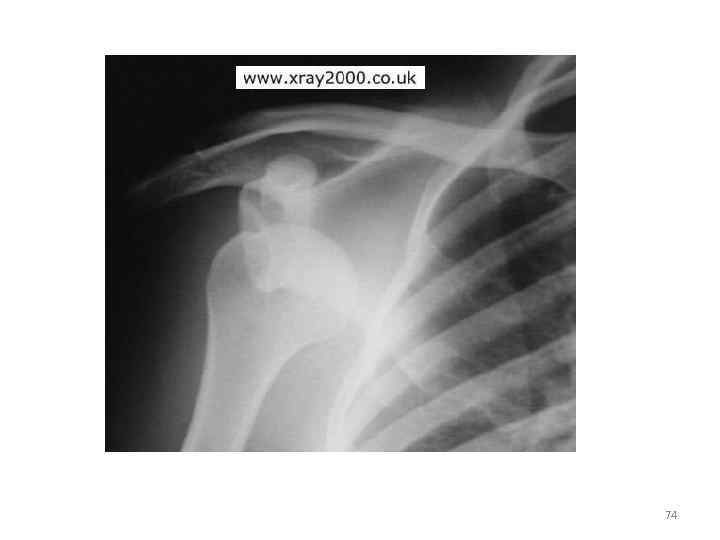

74

• На рентгенограмме области правого плечевого сустава в задней проекции определяется: полный передний вывих в плечевом суставе. 75